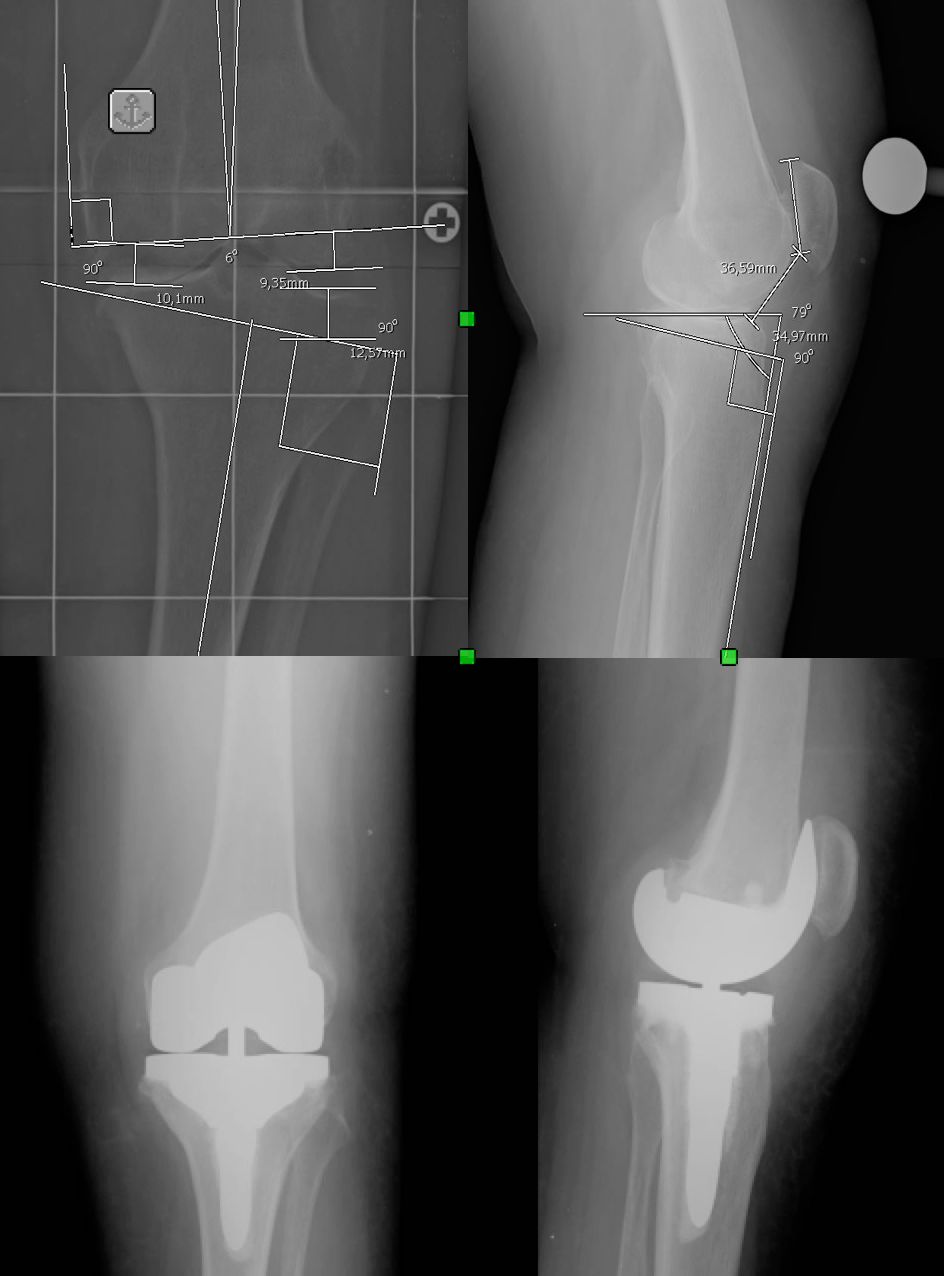

Il Dr. Giuntoli si è laureato in Medicina e Chirurgia nel 2014 presso l’Università degli Studi di Firenze e successivamente nel 2020, ha conseguito la Specializzazione in Ortopedia e Traumatologia presso l’Università degli Studi di Pisa con votazione di 110/110 e Lode, discutendo la tesi: “I sensori di pressione nella Protesi Totale di Ginocchio: confronto clinico e funzionale mediante Gait Analysis tra la tecnica convenzionale e il sistema VERASENSE”. Dal 2021 al 2024 ha svolto attività clinica, chirurgica ed universitaria presso la U.O. Ortopedia e Traumatologia I Universitaria dell'Azienda Ospedaliero Universitaria Pisana (AOUP) nell'Ospedale di Cisanello di Pisa Da gennaio 2023 svolge attività di docenza di ecografia muscoloscheletrica diagnostica e procedurale (infiltrativa) presso la scuola SIUMB di Pisa, di cui è anche docente dal 2024 presso l'Università di Pisa. Attualmente Dirigente Medico presso il CESAT (Centro Eccellenza Sostituzione Articolare Regione Toscana) - Ospedale San Pietro Igneo di Fucecchio, presso la quale svolge la maggior parte dell'attività clinica, chirurgica e di ricerca soprattutto nell'ambito della protesica di anca e ginocchio e dell'artroscopia di ginocchio. Da settembre 2023 svolge attività chirurgica anche presso la casa di cura privata San Rossore di Pisa e la casi di cura privata San Paolo di Pistoia. Istruzione e Formazione: • Laurea in Medicina e Chirurgia presso Università degli Studi di Firenze in data 28/10/14 • Specializzazione in Ortopedia e Traumatologia presso Università degli Studi di Pisa in data 17/11/20 • Il Dott. Michele Giuntoli ha partecipato a numerosi corsi di aggiornamento e perfezionamento in Italia e all'estero e collabora, attualmente, con le principali società scientifiche ortopediche nazionali ed internazionali • In qualità di relatore ha preso parte a diversi congressi e seminari ed è autore di diverse pubblicazioni scientifiche pubblicate su riviste del settore nazionali ed internazionali Dal 2015 al 2020 ha svolto attività di formazione c/o la Scuola di Specializzazione in Ortopedia e Traumatologia dell’Università degli Studi di Pisa (sotto la direzione del Prof. Lisanti e del Prof. Capanna effettuando attività clinica e chirurgica di Ortopedia e Traumatologia maggiore e minore in qualità di Specializzando presso le U.O. di Ortopedia e Traumatologia I (Dir. Prof. Scaglione) e II (Dir. Prof. Capanna) della medesima Università. Nel 2019 e nel 2020 ha frequentato in qualità di Specializzando la U.O. di Ortopedia e Traumatologia dell'Ospedale F. Lotti di Pontedera (Dir. F. Carnesecchi), dell'Ospedale Versilia di Lido di Camaiore (Dir. M. Manca) ed anche presso l'Ospedale di Livorno (Dir. A. Augusti), svolgendo prevalentemente attività chirurgica di Ortopedia e Traumatologia maggiore e minore. Nel 2018, in qualità di specializzando, ha effettuato una fellowship internazionale presso il Dipartimento di Chirurgia Ortopedica e Bio-ingegneria della Scuola di Medicina della Stanford University (Palo Alto, California, USA) svolgendo gran parte dell'attività di ricerca sulla chirurgia protesica di ginocchio al VA Health Care System di Palo Alto sotto la supervisione del Prof. Pier Francesco Indelli. Ha acquisito nell'anno 2021 competenze ecografiche per l'apparato muscolo-scheletrico ottenendo il diploma nazionale SIUMB. Premi e riconoscimenti: •Vincitore Borsa di Studio OTODI Young Conseguita presso il 50° Congresso Nazionale OTODI (Sorrento, 23-24 Maggio 2019) in data 24 maggio 2019 con la presentazione Elettronica “Protesi totale di ginocchio primaria total stabilizer: risultati clinici e strumentali a breve-medio termine” Pubblicazioni • https://www.researchgate.net/profile/Michele_Giuntoli • https://scholar.google.com/citations?hl=it&user=TY6iufsAAAAJ • https://pubmed.ncbi.nlm.nih.gov/?term=giuntoli%2C+michele%5BAuthor%5D&sort= Enti e società scientifiche: - SIOT (Società Italiana di Ortopedia e Traumatologia) - OTODI (Ortopedici Traumatologi Ospedalieri d'Italia) - ESSKA (European Society of Sports Traumatology, Knee Surgery and Arthroscopy) - EKA (European Knee Associates) - SIUMB (Società Italiana in Ultrasonologia in Medicina e Biologia). Abilitazione: • Ordini dei Medici Chirurghi e degli Odontoiatri (FNOMCEO) n. 2233 iscritto il 19/02/2015

• Chirurgia del ginocchio

• Chirurgia protesica con robot

• Protesi ginocchio